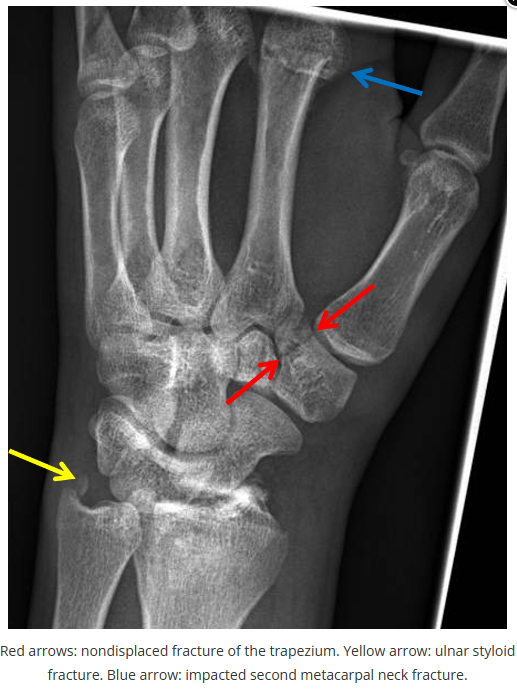

这些腕与手的骨折X线片如果没有标注箭头,你还能识别出来吗?

X线读片是骨科医生的基本功。

今天是腕部与手的X线片。所有X线片都

带有标注和说明

,可以选择长按图片,

自动翻译相关说明

。